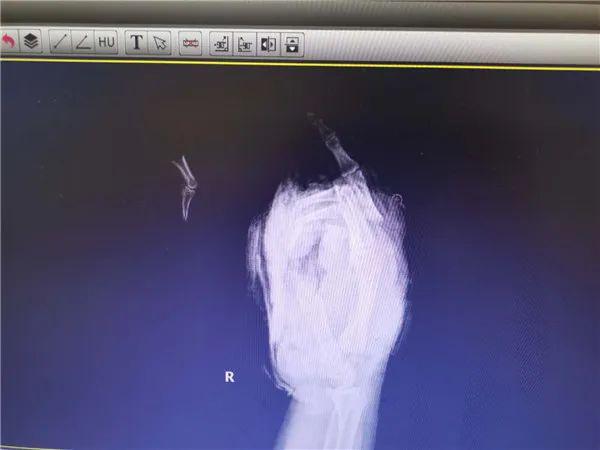

2 月 11 号下午两点,卢先生一家去上坟,他第一次点鞭炮以为没点着,再去点第二次时就不小心被炸伤了。" 当时血肉模糊,整个掌骨全部脱骨,手掌里面都没有肉了,我当时都要吓晕了," 回忆丈夫受伤的情景,岑女士还是很后怕。

目前卢先生已经完成初步接骨复位,等待一段观察期后还要进行第二次手术。